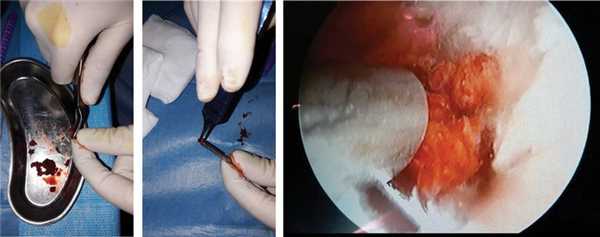

Далее под артроскопическим и рентгеновским контролем проводили 3 спицы: одна — осевая, проходящая сразу через дистальный и проксимальный отломки ладьевидной кости. Две другие спицы проходили только через дистальный отломок. Затем из крыла подвздошной кости брали губчатый костный трансплантат по типу «стружки», средний размер одного костного трансплантата — 0,2×0,2 см (рис. 4, а). Рис. 4. Обработка губчатого костного аутотрансплантата (а); заполнение шахты костной «стружкой» (б), введение костных трансплантатов в зону ложного сустава (в). Шахту заполняли костными трансплантатами (см. рис. 4, б) и вводили в зону ложного сустава (см. рис. 4, в) через ЛуСП.